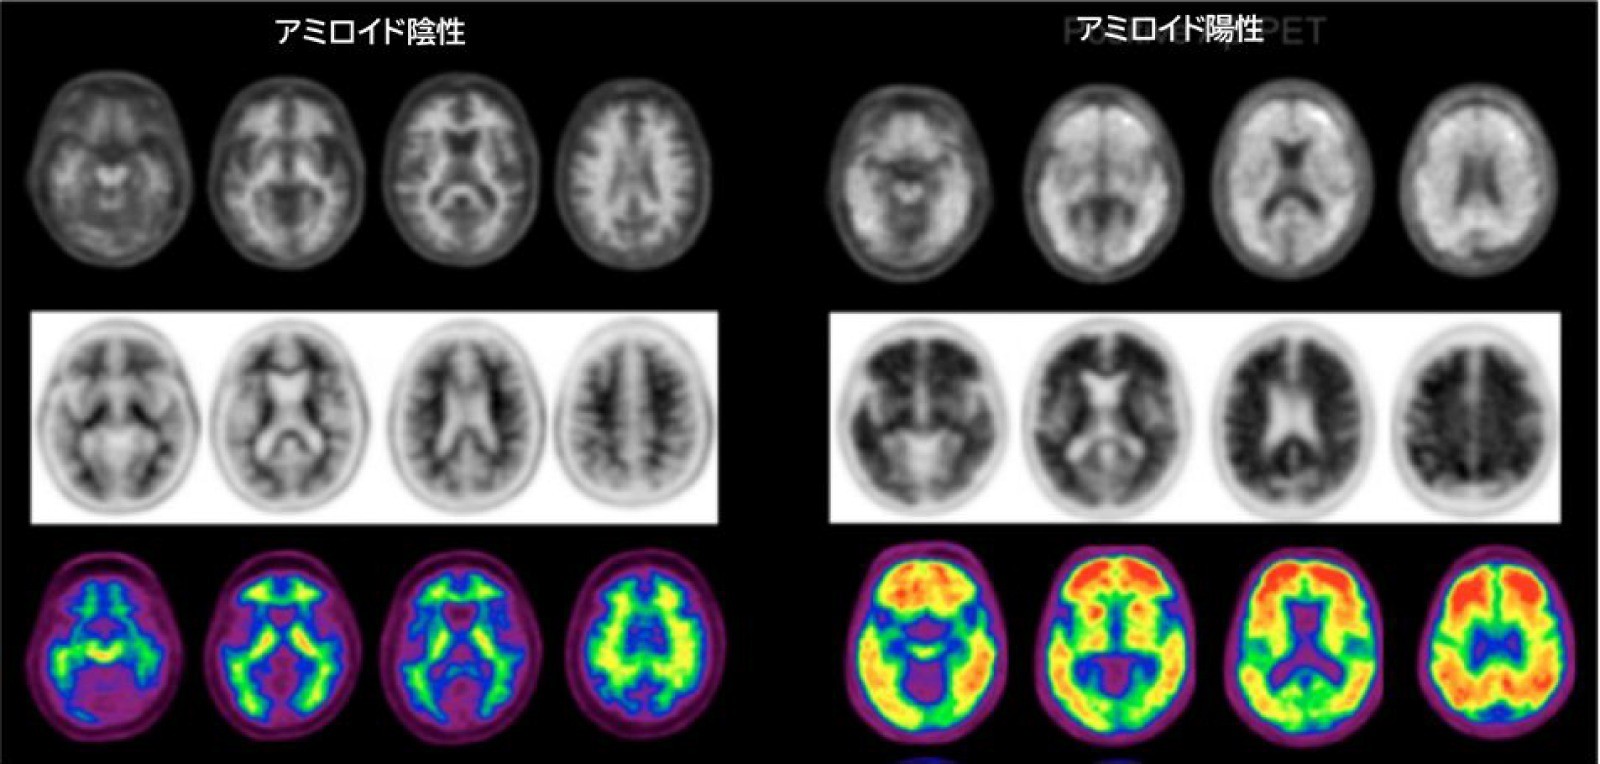

アルツハイマー病は脳内にアミロイドβ蛋白が蓄積し、その結果、神経細胞死が起こり、脳機能が低下するとされています。もともと、アミロイドβ蛋白は正常な脳内でも産生・分解されており、その平衡が崩れると異常にアミロイドβ蛋白が増加し、固まった異常蛋白がプラークとなり脳内に沈着して神経細胞死を起こしてしまいます。実際に認知症状を発症する20年ほど前から、アミロイドβ蛋白の蓄積は起こっていると考えられており、早期に治療介入することが重要と思われます。

最近、保険承認された、抗アミロイドβ抗体薬である、レカネマブやドナネマブは蓄積した異常なアミロイドβ蛋白を除去する作用がある薬です。ただし、症状の改善効果があるわけではなく、症状の進行抑制効果を期待して使用する薬剤であることには注意が必要です。厳格に適応患者像も決められており、症状が進行した状態では使用することができません。また、投与前には、アミロイドPET検査や髄液検査で、アミロイドβ蛋白の異常蓄積を確認する必要があります。

図は、Chapleau M, et al. J Nucl Med 2022;63(Suppl 1):13S-19Sより作成